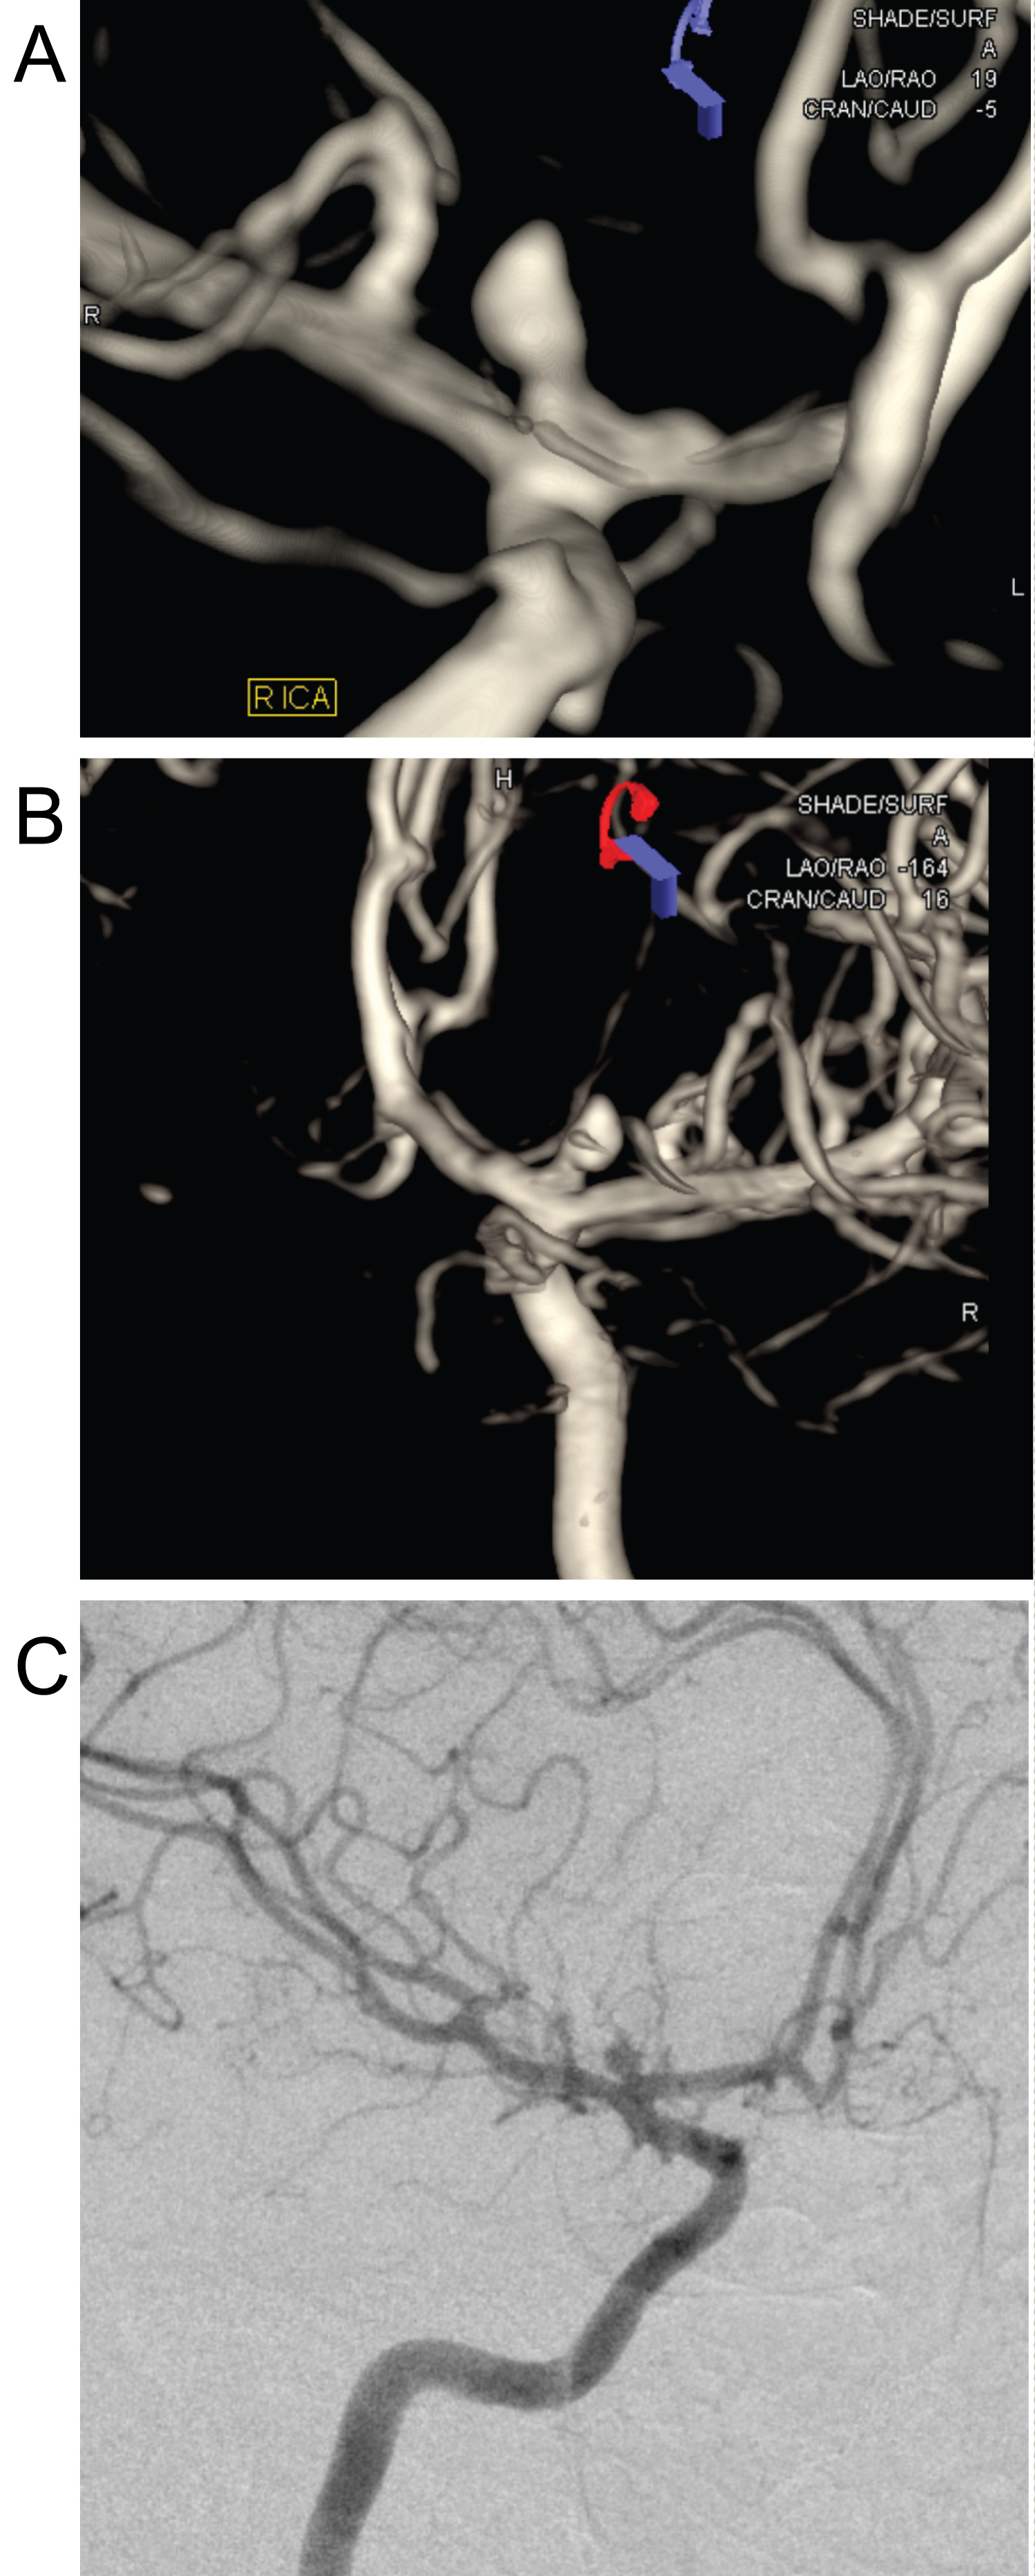

27-year-old female patient who was brought to the Emergency Department of our hospital with the complaints of severe headache and vomiting. Her general condition was moderate, she was conscious, disorientated, and cooperative. Pupils were isochoric, bilateral light reflex was positive, and there was no lateralized motor deficit. Glasgow Coma Score was evaluated as 14 points. Blood pressure was measured to be 130/80 mmHg, pulse was 90/min, respiratory rate was 14/min, and fever measured 36 centigrade degrees. Head CT reported as hyperdense appearance compatible with intraventricular hematoma in both lateral ventricles and at the level of 3rd and 4th ventricle (Figure 1). Disseminated subarachnoid hemorrhage and additionally widespread calcification across bilateral basal ganglia, thalamus, and subcorticalwhite matter detected. Patient first taken to the OR to place an external ventricular drainage (EVD) catheter (Figure 2). Then DSA performed which revealed saccular aneurysmatic filling with 5*3 millimeters in diameter at the apex of the right Internal Carotid Artery just before theM1 segment of Middle Cerebral Artery. Endovascular coil placement was performed for aneurysm treatment (Figure 3). Then patient was taken to the neurosurgery intensive care unit for post-operative (PO) close follow-up. On the PO-5th day, she was taken to the in-patient floor due to wellness in her general condition. Control angiography showed successful closure of the aneurysm (Figure 4). Patient followed up three days with EVD closed as the clarification of the color of the cerebrospinal fluid in the catheter and resorption of the intraventricular hemorrhage in the control tomography observed (Figure 5). As no changes seen in the clinical status EVD catheter removed and patient discharged to home on the PO-12th day.

Figure 3: DSA image showing saccular aneurysmatic filling with a diameter of 5*3 millimeters at the apex of the Right Internal Carotid Artery, just before the M1 segment of the Middle Cerebral Artery. View Figure 3

Figure 4: Control DSA image after endovascular coil placement for aneurysm treatment. View Figure 4